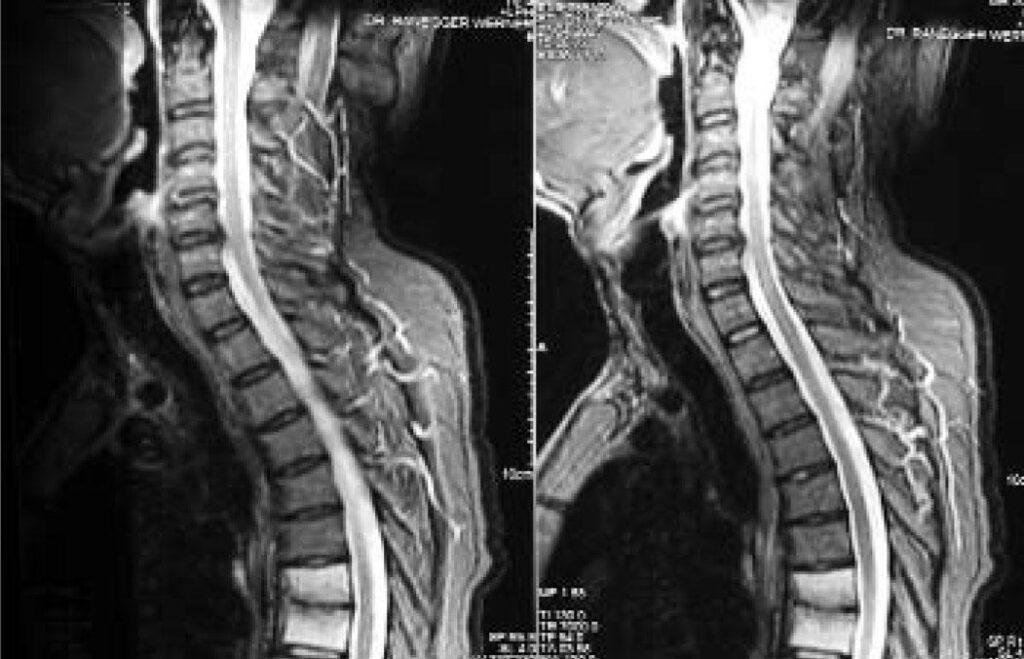

Spondylitis is an autoimmune disorder. This means spondylitis’ underlying cause is a person’s immune system mistakenly attacking its own tissues. A type of arthritis, spondylitis’ inflammatory effects primarily affect certain parts of the spine. Over time, this chronic inflammation in the spinal joints and tissues causes stiffness. In severe instances, the bones in the spine fuse together.

There are several types of spondylitis, including ankylosing spondylitis (AS), enteropathic arthritis, psoriatic arthritis, reactive arthritis, undifferentiated spondyloarthritis, juvenile spondyloarthritis, and peripheral spondyloarthritis.